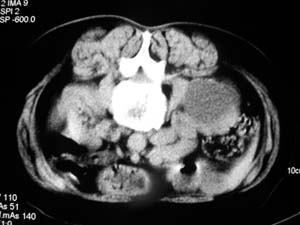

我们主要在ct引导下进行各种囊肿的穿刺引流,对于肾囊肿治疗的较多.穿刺成功后尽量抽尽囊液并且记录数量,抽尽后注入造影剂看看是否与尿路相通,然后用1/4的比例注入无水酒精进行硬化.跟踪观察治愈率达98%以上.